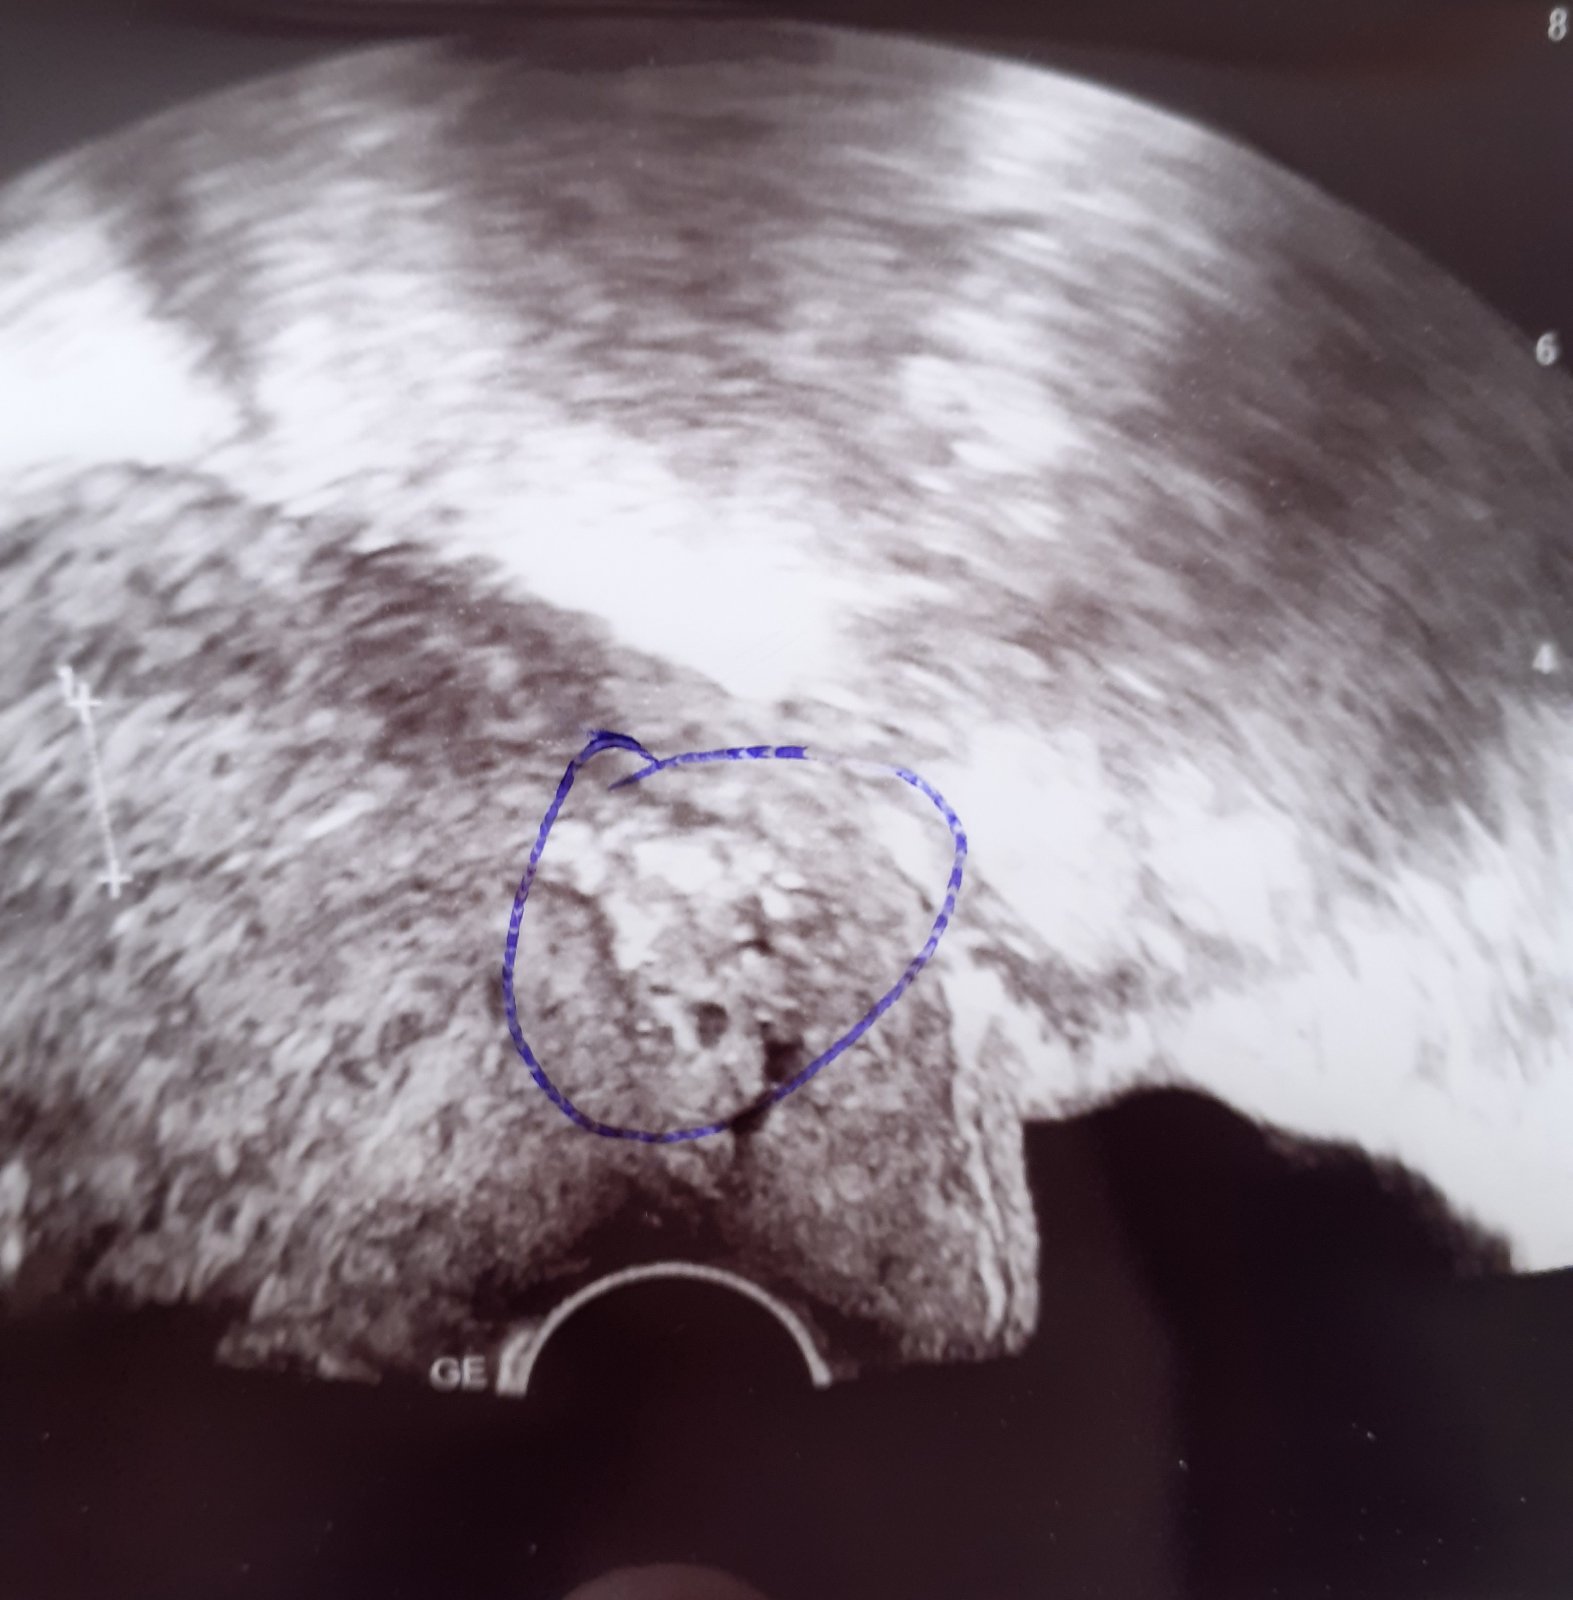

při gynekologické prohlídce pan doktor přes ultrazvuk zjistil "něco" v děložním hrdle, ani s menstruací tento útvar nezmizel. V dubnu jdu na hysteroskopii.

Samozřejmě dle utz nelze říct, o co se jedná, ale i přesto bych se chtěla zeptat, jaké jsou možnosti, co by tento nález mohl být?

také by se například mohlo jednat o kalcifikace (vysrážená vápenatá ložiska) nebo o tzv. Nabotovy žlázky (Ovula Nabothi) - obojí zcela nerizikové.